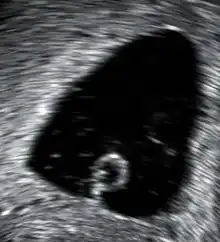

| An ultrasound showing a gestational sac containing a yolk sac but no embryo | |